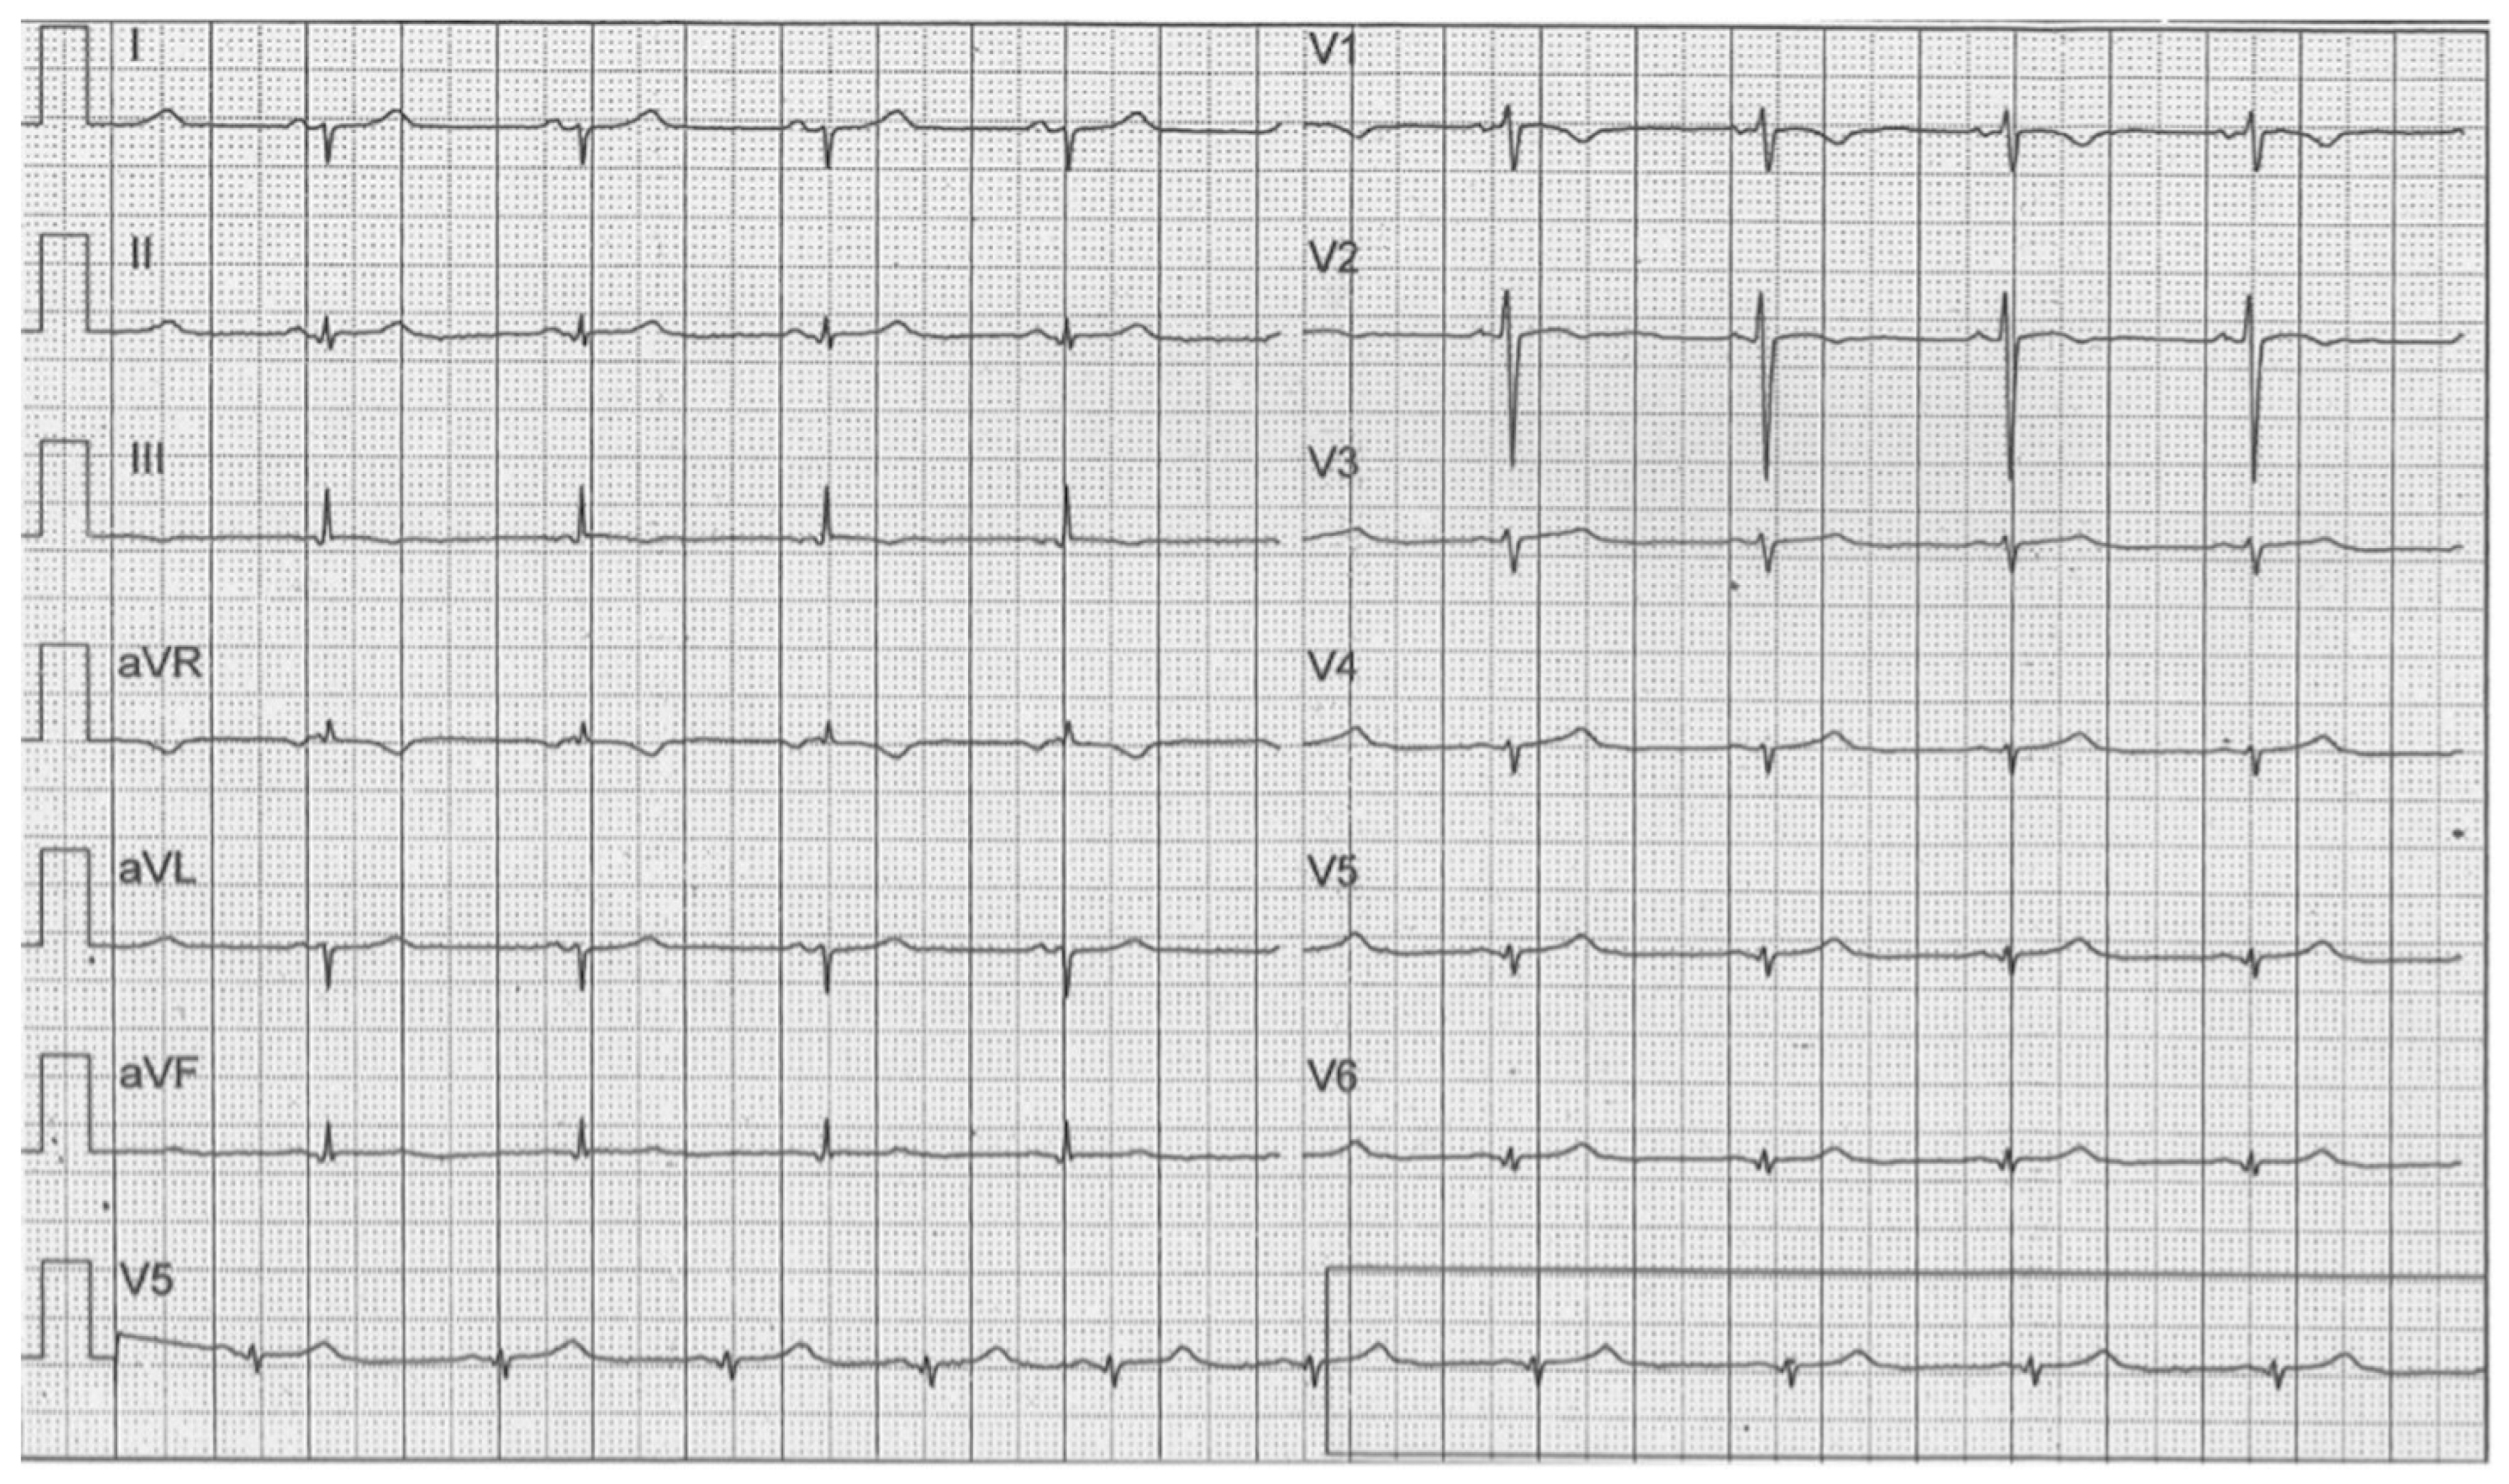

4. Case 3